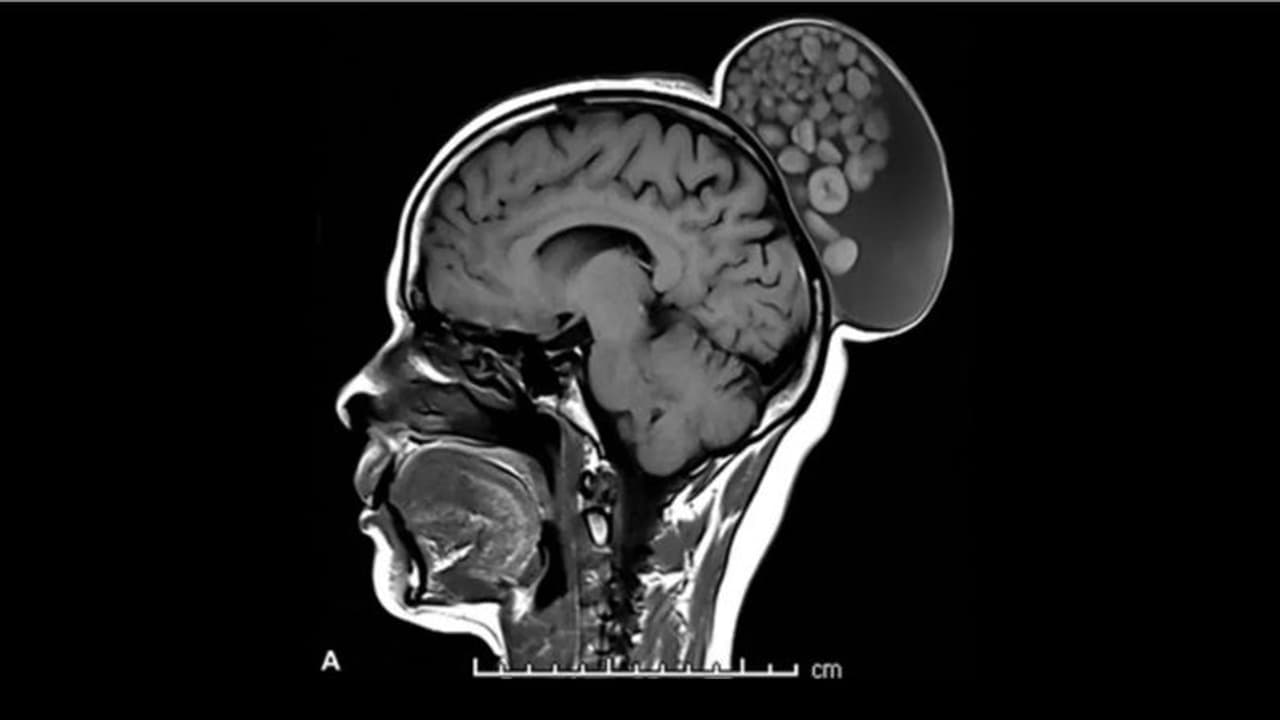

52 കാരിയായ സ്ത്രീ കുട്ടിക്കാലം മുതൽ തലയോട്ടിയിൽ മുഴയുമായി ജീവിച്ചു വരികയായിരുന്നു. എന്നാൽ ഇതുവരെ അവർ ചികിത്സ തേടിയിരുന്നില്ല. മുഴയിൽ നിന്ന് വേദന അനുഭവപ്പെട്ടിരുന്നില്ല. എന്നാൽ വീക്കം ഏകദേശം ആറ് ഇഞ്ച് നീളവും നാല് ഇഞ്ച് വീതിയിലും വളർന്നിരുന്നു. എംആർഐ സ്കാൻ ചെയ്തപ്പോഴാണ് തലയുടെ പിൻബാഗത്ത് മുടി കെട്ടി വച്ചതുപോലെ ബണ്ണിന്റെ വലിപ്പത്തിലുള്ള മുഴ കണ്ടെത്തിയത്. വെള്ളവും മുടിയും പ്രോട്ടീനായ കെരാറ്റിൻ ബോളുകളും നിറഞ്ഞ നിലയിലായിലായിരുന്നു നീക്കം ചെയ്ത മുഴ ഉണ്ടായിരുന്നതെന്നും ഡോക്ടർമാർ വിശദീകരിക്കുന്നു.